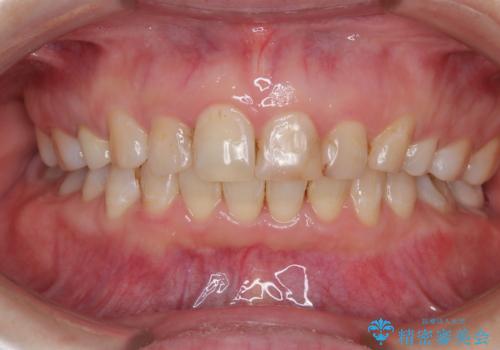

- 前歯のデコボコを治したいとのことで来院された患者様です。

上下顎ともに歯列全体の後方移動とIPR(歯と歯の間を削る)によってデコボコが解消するように設計し、インビザラインにより治療を行うこととしました。